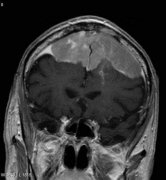

岩斜区脑膜瘤手术风险大?显微

岩斜区脑膜瘤 仍然是外科手术的巨大挑战。这些肿瘤以缓慢、持...